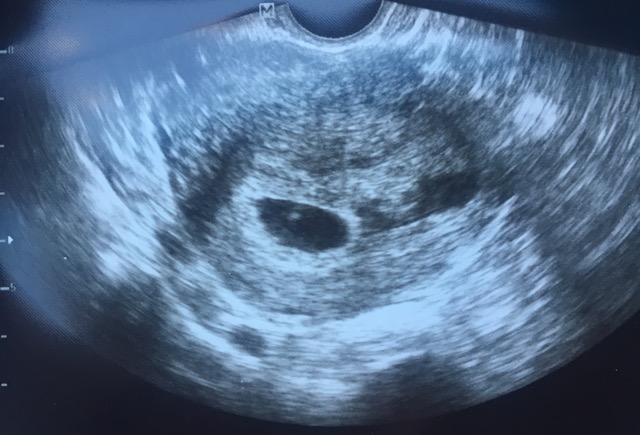

Fluid in uterus?

Has anyone has this happen? I went to a 6 week ultrasound today and they saw "fluid" next to the sac. I am a mom of fraternal twins already. Is this a vanishing twin? She said it could be or it could be just unexplainable fluid. Would love to hear from anyone else with similar sonograms!